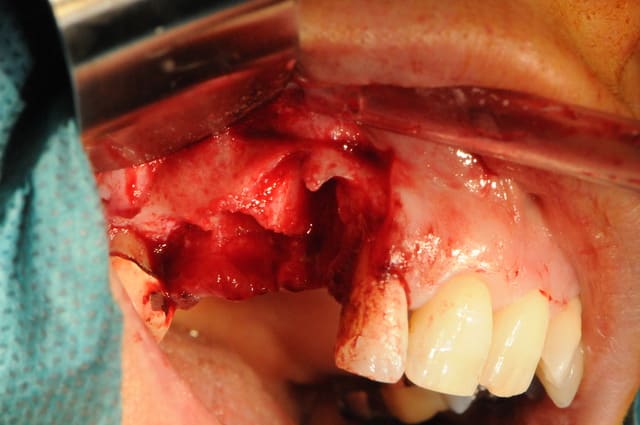

-fracture 25

-infection

-extraction (oups la ccm sur implant s'est descellée...)

-pas de pose d'implant car destruction de la paroi vestibulaire sur près de 5 mm

-pas de lambeau mais décollement vestibulaire muco-périosté à travers l'alvéole d'extraction et interposition d'une membrane de Collagen AT entre l'os et le périoste

-comblement BioOs et recouvrement avec même type de membrane

-conjonctif pédiculé tracté (comme j'ai pu) pour fermeture du site d'"extraction.